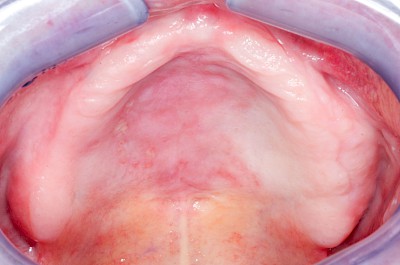

Talgdrüsen sind wichtig für die Haut und machen diese widerstandsfähig gegen Reibungen aller Art. Die Schleimhaut jedoch braucht keine Talgdrüsen, da der Speichel die Oberfläche gut befeuchtet und damit gegen Reibung schützt. Trotzdem kommen – bei manchen Menschen durchaus sehr ausgeprägt – solche ektopen (außerörtlichen) Talgdrüsen vor. Diese haben keinen Krankheitswert und müssen nicht behandelt werden. Ektope Talgdrüsen zeigen sich häufig flächig verteilt und fallen vor allem auf im Bereich der Wangenschleimhaut oder der Lippen.

Beispiele8 Bilder